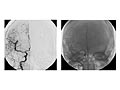

Una angiografía de la cabeza y del cuello es una prueba de rayos X que utiliza un tinte especial y una cámara (fluoroscopio) para tomar imágenes del flujo de sangre en los vasos sanguíneos de la cabeza y del cuello. Puede utilizarse una angiografía del cuello (angiografía carotídea) para observar las grandes arterias en el cuello que se dirigen al cerebro. Puede utilizarse una angiografía de la cabeza (angiografía cerebral) para observar las venas o las cuatro arterias (estudio de cuatro vasos) que llevan sangre al cerebro.

Durante una angiografía, un tubo delgado y blando que se llama catéter se coloca en un vaso sanguíneo de la ingle o justo por encima del codo. El catéter es guiado a la zona de la cabeza y el cuello. Luego, se inyecta un tinte de yodo (material de contraste) en el vaso sanguíneo para hacer que la zona se vea de manera nítida en las imágenes radiográficas. Las imágenes de la angiografía pueden presentarse en placas de radiografías regulares o pueden guardarse como imágenes digitales en una computadora.

Una angiografía puede detectar una protuberancia en un vaso sanguíneo (aneurisma). También puede mostrar el estrechamiento o la obstrucción de un vaso sanguíneo que hace más lento o detiene el flujo de sangre. Puede verse un patrón anormal de los vasos sanguíneos (malformación arteriovenosa [AV]) o vasos anormales cerca de un tumor.